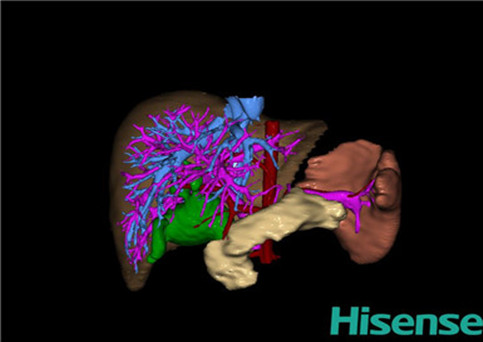

10、三维重建虚拟肝脏、胆道显像技术

三维虚拟肝脏技术是在二维影像学资料如CT等图像的基础上,通过三维重组软件和工具,比如青岛大学附属医院与海信医疗集团联合自主研发的海信计算机辅助手术系统(Hisense Computer Assisted Surgery,Hisense CAS),目前已投入临床并指导实际应用,利用该类系统对二维影像学的数据资料进行三维立体分析,重组形成立体的、有空间结构的、虚拟的肝脏三维图像。这项技术较传统的二维平面成像技术,有着明显的优势,3D虚拟肝脏技术可以构造出一个虚拟的、可视化的肝脏模型。通过对这种模型的观察,可以很容易地分辨出肝脏器官的组织结构、解剖特点,直观研究肝外胆总管的形态差异,明确肝内胆管的形态、走形、是否合并扩张、狭窄及结石,胰胆管合流的形态及共同通道内是否有狭窄、扩张和结石等病变情况,预先规划处理可能合并存在的肝内胆管扩张、狭窄或其他复杂胆道畸形,清晰地显示肝内脉管系统,包括门静脉、肝动脉及肝静脉的走行、分支,并可多角度、全方位观察病变胆道与其周围重要血管尤其是伴行的门静脉之间的解剖关系,大大提高了外科医师在术前对肝脏内部各管道结构及其变异判断的精确性和可靠性,精准地对病变进行判断和评估,还可根据患者自身的病变特点,制定出合理、个体化的手术方案,最大限度地降低术中和术后并发症发生率,并术中导航实时指导手术,提高手术的精准性和成功率。

图10:先天性胆管扩张症囊肿型三维重建虚拟肝脏、胆道显像

a 图为术前二维CT扫描图像,箭头所示为肝内胆管扩张;b 图为CT经多平面重组技术(MPR)图像后处理所得的重建图像,可显示胆总管明显扩张合并肝内胆管扩张;c 图为MRCP显示胆总管呈囊柱状扩张,直径>1 0 cm,伴肝内胆管扩张;d 图示Hisense CAS三维重建清晰显示肝脏、胆道系统及其与门静脉、肝动脉、肝静脉等之间的空间解剖关系;e 图示Hisense CAS可从任意角度以不同脏器组合显示,明确胆道系统与其伴行的门静脉系统的空间解剖关系;f 图示胆道系统立体形态及与肝脏整体的空间关系,箭头处显示肝内胆管狭窄部位发生于左右肝管汇入肝总管处。术前规划需行肝内胆管扩大成形术。